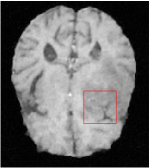

Qualitative comparison between conventional and Meta-learning methods are shown in Figure 1 and 3, which display the reconstructed MR images of the same slice for T1 and T2 respectively, we label the zoomed-in details of HGG in the red boxes. We observe the evidence that conventional learning is more blurry and lost sharp edges, especially in lower CS ratios. From the point-wise error map, we find meta-learning has the ability to reduce noises especially in some detailed and complicated regions comparing to conventional learning.